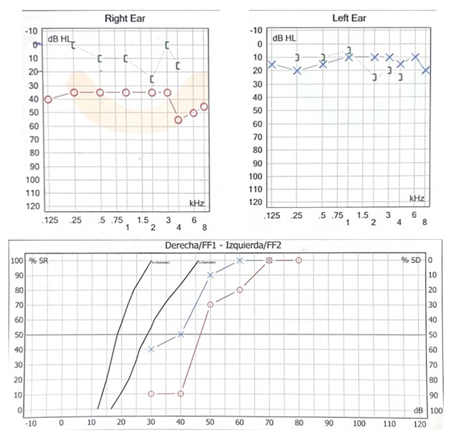

A la exploración física se palpa tumoración en nivel II de cuello derecho de aproximadamente 6 cm x 3 cm, de bordes regulares, de consistencia dura, no móvil, no dolorosa a la palpación, fija a planos profundos, y en cavidad oral se observa amígdala derecha grado IV, de apariencia lobulada, hiperémica, firme, cubierta por exudado blanquecino, no ulcerada, no sangrante, dolorosa a la palpación, que desplaza medialmente el paladar blando. (Figura 1).

Se realiza tomografía computarizada contrastada de cráneo y cuello; en la cual se observa a nivel de amígdala palatina derecha, una lesión isodensa a tejidos blandos de bordes regulares, que disminuye la luz de la vía aérea y desplaza al espacio parafaríngeo ipsilateral, que no realza al paso del medio de contraste (Figura 2).

La paciente fue sometida a una biopsia incisional de la lesión, se extrajo un espécimen de 3 x 1.9 cm, a la visión macroscópica de superficie rugosa, de coloración blanca grisácea y de consistencia blanda; dicha muestra se envió al servicio de patología para su estudio, con un resultado de Linfoma No Hodgkin difuso de centro folicular de estirpe de células “B”. (Figura 5). Al igual se realizó inmunohistoquímica la cual reportó CD-3, CD-10, CD-20, BCL-2, BCL-6 Y Ki-67 positivos. (Figura 6 y 7).

El tipo folicular de LNH que se demostró en el presente caso se encuentra con menor frecuencia, y el patrón de crecimiento de los linfocitos pequeños se caracteriza por folículos neoplásicos mal formados, constituidos por centrocitos y centroblastos. Desde el punto de vista inmunohistoquímico, los LNH foliculares revelan expresiones de CD 10. La tinción positiva con anticuerpos frente a la molécula antiapoptótica Bcl-2 y Bcl-6 es bastante común. La sobreexpresión del gen Bcl-2 inhibe la apoptosis en las células afectadas y consecuentemente resulta en la expansión incontrolable de los tejidos linfoides.10 Los LNH foliculares responden mal a la radioterapia, quimioterapia o combinación de ambas. Además, en aproximadamente un 40% de los casos puede observarse la transformación de la enfermedad en un subtipo de linfoma más agresivo, el LCDGB. La tasa de supervivencia global a los 5 años depende principalmente del estadío de la neoplasia en el momento del diagnóstico y varía entre un 50 a un 80% para los LNHs de la región maxilofacial. Por todo ello el diagnóstico temprano resulta imperativo.